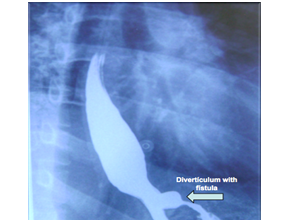

Ten months later he developed epigastric pain, irradiated to the back, mainly with food intake. An abdominal ultrasound reveled lithiasic cholecystitis. An esophagogram showed the passage of a double column of contrast material into the stomach and esophagogastric fistula was suggested (Figure 1). Endoscopy showed a diverticulum at the lower third of the esophagus with an impacted food bezoar that was extracted with foreign body tweezers and a fistulous path was found which communicated with the fundoplicated gastric fundus and confirmed the diagnosis (Figure 2). Due to the exacerbation of the symptoms, laparoscopic surgery was proposed to resolve both the gallbladder and the fistulous problems. The fundoplication was dismantled and the resection of the fistulous tract (Figure 3 & Figure 4) was performed at the lower third of the esophagus with articulated linear stapler. Fibrin sealant (Tissucol®) was applied to the proximal end of the fistulous tract, the closure was reinforced with suture in the gastric end of the resected fistula, Nissen fundoplication was done in the usual way (Figure 5) and finally cholecystectomy was performed. Recovery was uneventful with relief of dysphagia and odynophagia. At 5year follow-up, the patient is asymptomatic without reflux and without dysphagia.

Figure 1 Esophagogram with double column of barium image.

The most commonly known esophageal fistulas are those that communicate the esophagus to the trachea and are usually birth defects. The abnormal communication between the esophagus and the stomach is a very unusual situation that occurs as a complication in postoperative fundoplicated patients. Until now only 15 cases have been reported in the literature.1 Factors mentioned as related to this problem are preexisting esophageal ulcers that later erode the esophageal wall, persistent gastroesophageal reflux due to fundoplication failure,2,3 esophageal carcinoma4 or even Crohn's disease.5 There is little mention about failures during surgery such as those that cause necrosis around the fixation suture points for the fundoplication,6‒8 trauma during dissection or inadequate traction of the esophagus or stomach without free perforation, but that erode the esophageal or gastric wall causing small infections that finally give rise to the fistula. This phenomenon is a probable cause in the case reported with the use of suture with pledgets for the fundic plicature.8  Some of these patients have received medical treatment with pump inhibitors to alleviate symptoms and although endoscopic clip application to close the fistula has been reported, surgery is the most effective treatment to close the fistula, and redo the Nissen fundoplication.2,9,10 All the cases described in the literature solved the problem by open surgery, but we believe that minimal-invasive surgery can be a better approach. In experienced hands, laparoscopy is a good therapeutic option because it allows dismantling the previous surgery and performing the new fundoplication with minimal complications and the benefits of mini-invasive surgery. It permits accurate visualization of the fistulous tract and allows its adequate resection with a better postoperative recovery. Endoscopic assistance as used in this case can be useful. As far as we know, this is the first case described of a total laparoscopic correction of this problem. In most cases the diagnosis occurs two to three years after the first procedure. This may be due to the fact that, unlike esophageal or gastric perforation, the fistula does not cause an acute problem and symptoms of persistent dysphagia and odynophagia following antireflux surgery are progressive and are mainly attributed to other causes.  Although endoscopy is the gold standard for diagnosis, the radiologic image in the esophagogram seems to be constant in all reported cases. All show a double column of contrast material1,4 at the lower third of the esophagus as it enters the stomach. Because of this image, the condition has been named in some of the reports as “double lumen esophagus”. We think that the pathognomonic feature of the esophagogram that must be recognized is this double column at the lower third of the esophagus in patients with dysphagia after Nissen fundoplication. Tomography is a useful instrument for the study of fistulas, but in this particular case it was not necessary due to the evidence obtained with the barium esophagogram study wich we consider pathognomonic.